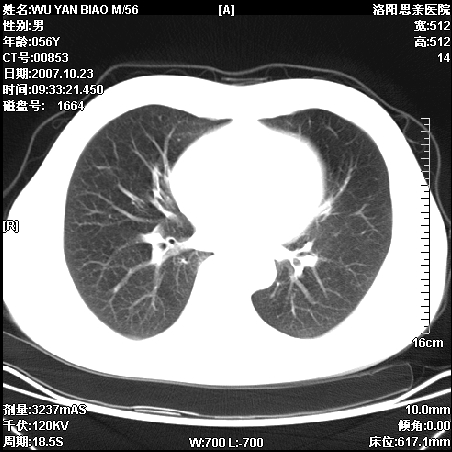

标题: CT10160:M56Y,体检发现,病人无不适,病人随访中 [打印本页]

标题: CT10160:M56Y,体检发现,病人无不适,病人随访中

后上纵隔占位,与肺交界清,宽基底附着脊柱,密度均匀,局部骨质无明确改变.

考虑;神经源性肿瘤,---起源交感n链?,不除外肠源性囊肿.

与纵隔关系密切,密度均匀。只能考虑:后纵隔神经原性肿瘤!

1、病灶在后纵隔脊柱旁沟内,此处是神经原性肿瘤的好发部位

2、病灶边缘光滑整齐,更说明病灶来于纵隔,由于有胸膜的包裹所以才导致这么光滑的边缘

3、病灶内的密度均匀